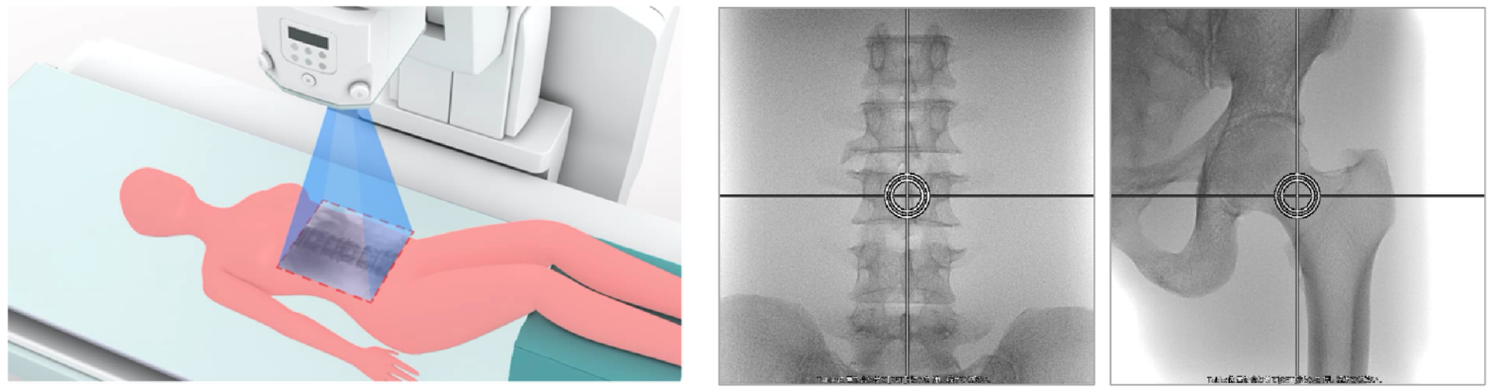

低剂量透视模式下的位置确认(左:腰椎 右:股骨)

SONIALVISION SMIT上搭载的骨密度功能(BMD)具有便捷快速的检查流程。患者无需转移检查房间即可在SONIALVISION SMIT上完成X光拍片及骨密度检查。